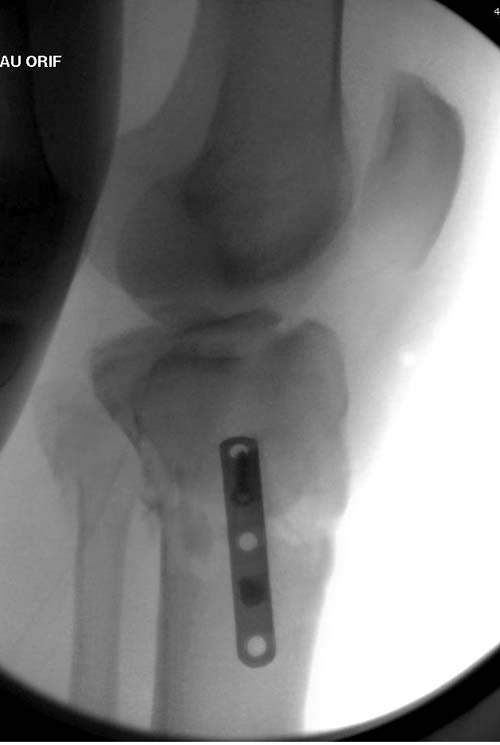

Вытяжение или наружный фиксатор “бедро-голень в виде дельты”. Фиксатор дает свободу, и если условия позволяют, можно отпускать домой. Но главное - надо ожидать проявления “wrinkle sign”! После дистракции можно делать КТ исследование, иначе нестабильные фрагменты искажают данные. Доступ делается по топографии расположения фрагментов, а 3Д картина лучше покажет расположение смещенных мыщелков.

Еще одно дополнение, некоторые в прочтении перелома медиального мыщелка делают типичные ошибки, например, редко переломы медиального мыщелка бывают “только медиальными”, а часто с наличием сложного, заднего компонента, который часто смещается кзади.

На боковом рентгене, явный задний смещенный компонент. КТ поможет увидеть "вершину" перелома, куда надо поставить антискользящую пластину из заднего или задне-медиальнего доступа. Для стабилизации боковой колонны традиционный боковой доступ через Girdle tubercle с длинной блокирующей пластиной. Одна задняя подпорка не удержит медиальную колонну, требуется длинная медиальная пластина.